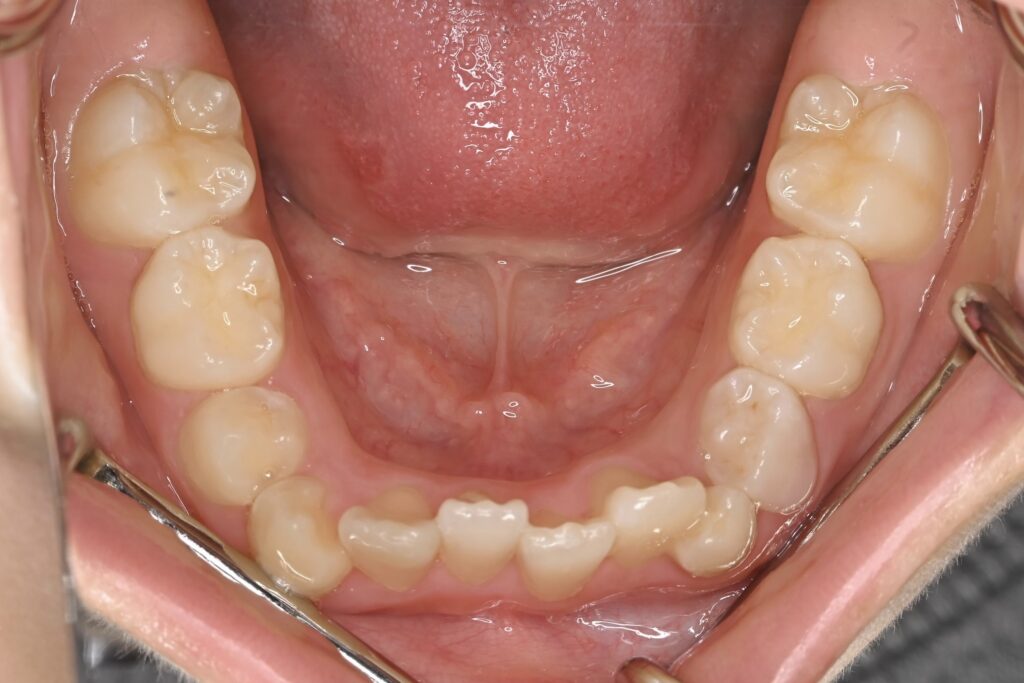

BEFORE

AFTER

主訴 通っている歯医者で矯正した方がいいと言われて気になっている。下の前歯がでこぼこしている。

診断名・主な症状 下顎前歯の叢生を伴う過蓋咬合

治療内容 上下の歯並びの幅を拡げつつ、前歯の関係を改善しました。

使用装置 急速拡大装置

リンガルアーチ

機能的矯正装置(マイオブレース)